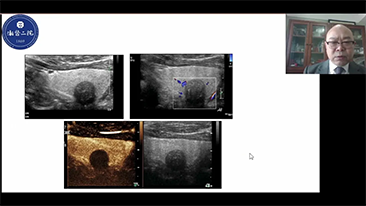

Solusi Pencitraan Umum Resona dari Mindray membantu para dokter mewujudkan diagnosis dan hasil pengobatan yang lebih akurat dan efisien melalui pemerik aplikasi subdivisi yang komprehensif dan alat bantu aplikasi klinis yang efisien.

Lingkungan medis saat ini telah menjadi lebih kompleks, dengan peningkatan jumlah kasus yang sulit dan beban kerja.